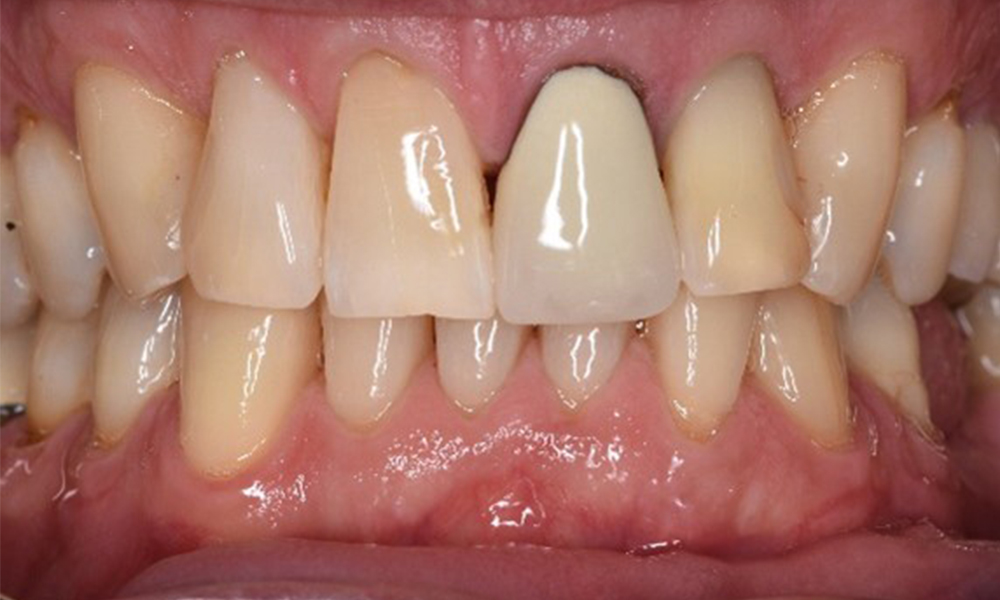

In the medical history, the 55-year-old patient states that he has no systemic disease and is not taking any medication. The patient’s lifestyle is similarly unremarkable. The patient has a few tooth restorations and two implants (2nd and 4th quadrants). On the basis of current findings, gingivitis is identified in an otherwise stable periodontal condition on the reduced periodontium (stage III, grade A).

Despite the stable condition, it is also important for this patient to be given motivation/instruction. Particular attention should be paid to correct care for implants. Here in particular, good at-home maintenance can have a significant impact on the long-term stability of oral and implant health.

In terms of instruments, specific procedures are required for use with implants. In order to preserve the surface of the implant while cleaning it effectively, it is essential to choose suitable powders and instruments, such as the targeted use of air polishing devices with special periodontal tips. Which powder is most suitable can be determined according to the needs and risk. For example, in addition to the appropriate degree of abrasion, dietary requirements (including sugar-free, low-salt) may also be taken into account.